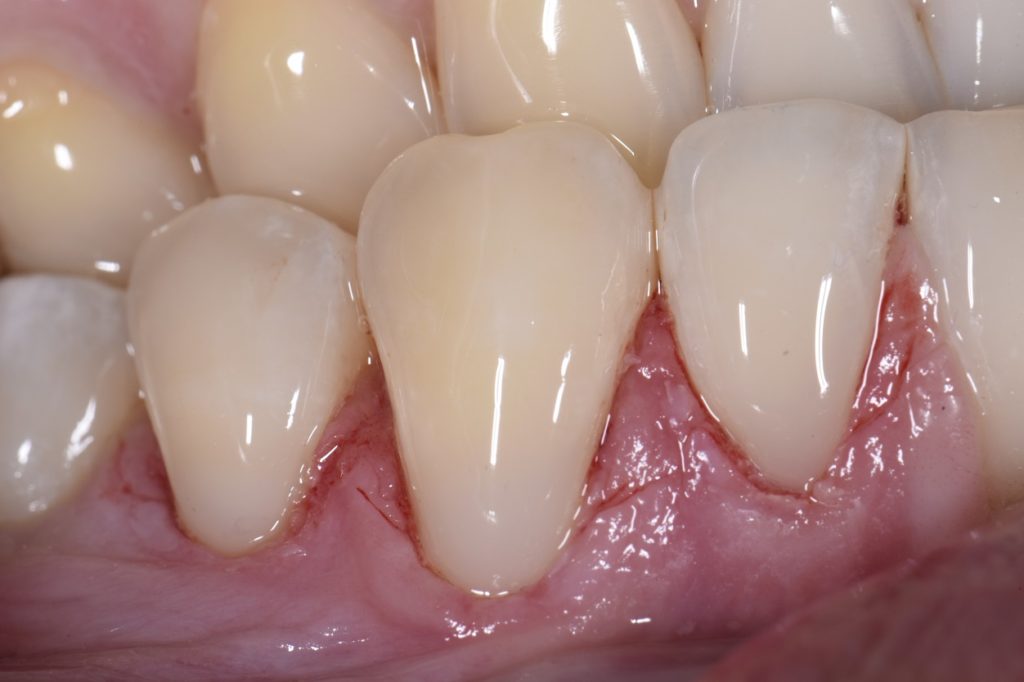

Root abrasion lesions restored and protected